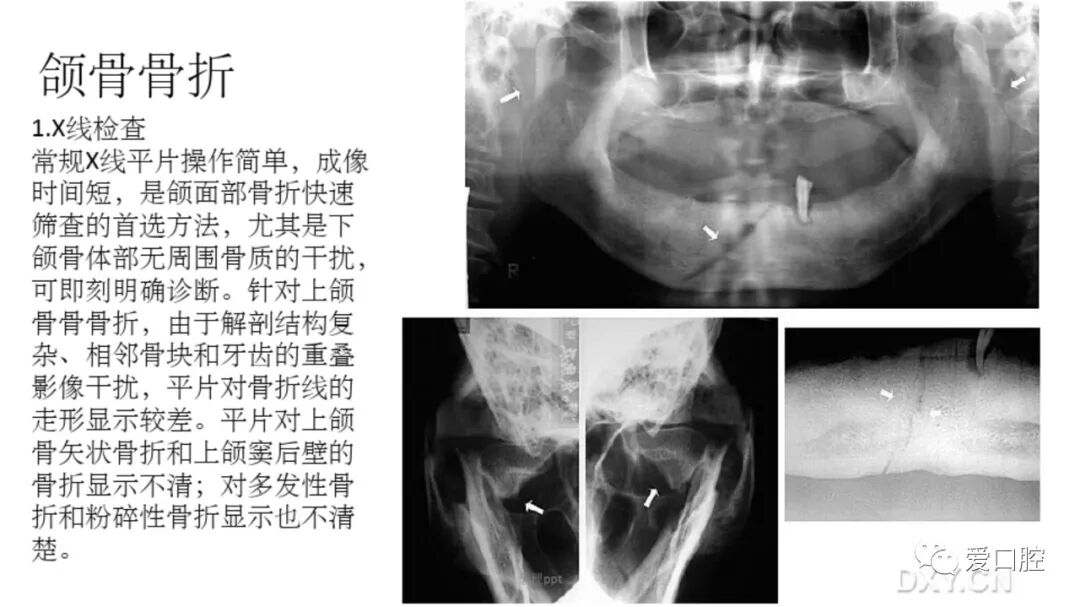

口腔小技巧 | 口腔科常见的病例影像!